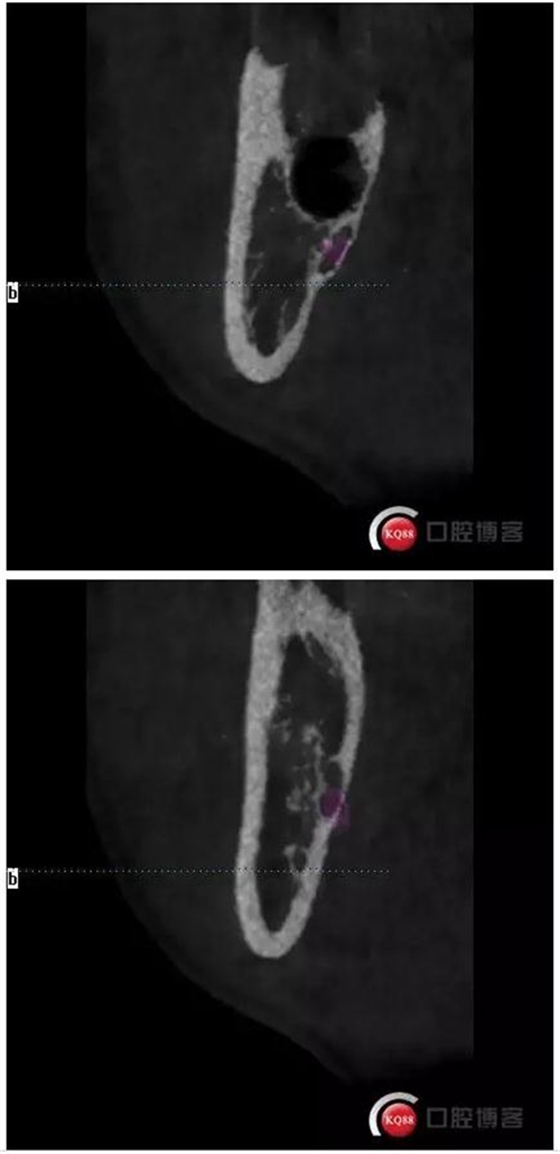

下面拔除后的片子,可以清楚的看到,牙根穿破神經(jīng)管。

1500633362_825152.jpg拔除后。 可以看到神經(jīng)管皮質(zhì)骨的不連續(xù)。